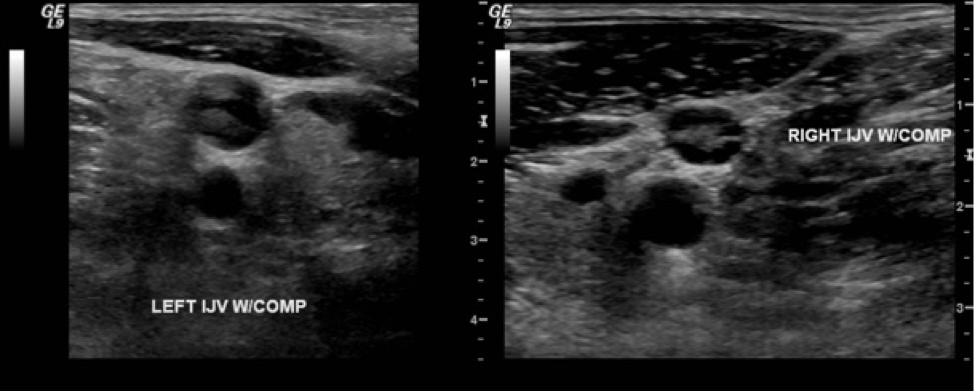

Bilateral upper extremity Doppler venous ultrasonography showed acute DVTs of the bilateral internal jugular veins (Figure) and left subclavian vein. Findings of magnetic resonance venography of the brain were negative for cavernous sinus thrombosis.

Figure. Left and right internal jugular DVTs on Doppler venous ultrasonography imaging.